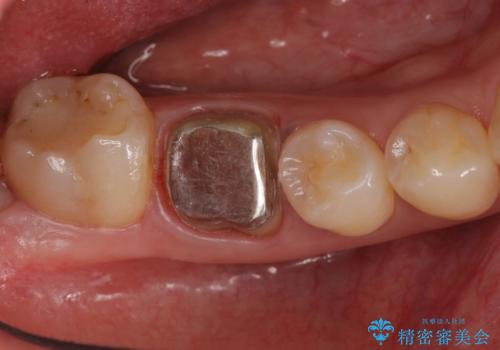

- 右下の奥歯に入れた銀歯を白くしたいとのことで来院されました。

根っこの治療がされていますが、症状もなくレントゲン画像で病変も確認できないため根管内には触れず被せ物のやり替えのみとなりました。